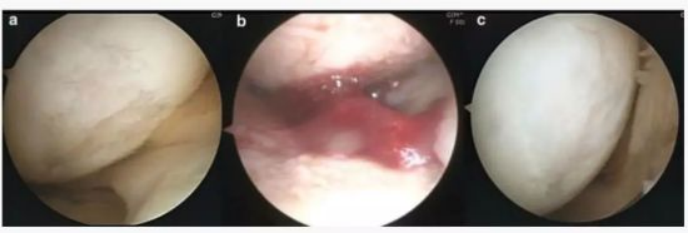

·研究结果:大多数患者在最终随访中的所有结果测量均有显著改善。。。。在第二次关节镜检查中,,,,14个(总共16个)的关节软骨没有退化,,只有5例患者的Kellgren-Lawrence评分恶化。。

下图a为治疗前关节镜检查结果,,可以看出软骨存在缺损。。。图b为脂肪间充质干细胞联合PRP治疗,,图c为治疗后结果,,,通过间充质干细胞治疗,,软骨得到了修复。。。